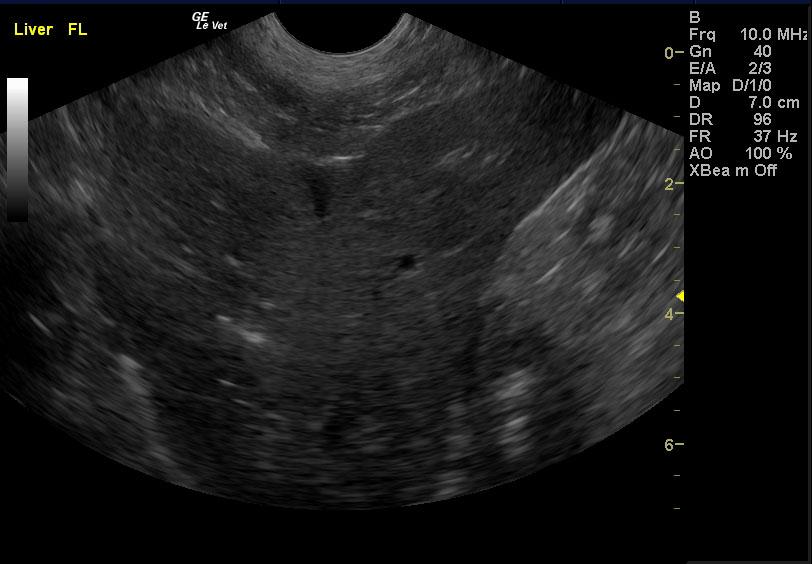

A 15 year old female spayed mixed canine with a history of decreased appetite, diarrhea, and ataxia was presented for evaluation of being unable to walk, weak and lethargic, anorexic, and possible seizures. Abnormalities on serum biochemistry were severely elevated liver enzyme activity, bilirubinemia, hypokalemia, and elevated pre-prandial bile acids. Systolic blood pressure was normal.